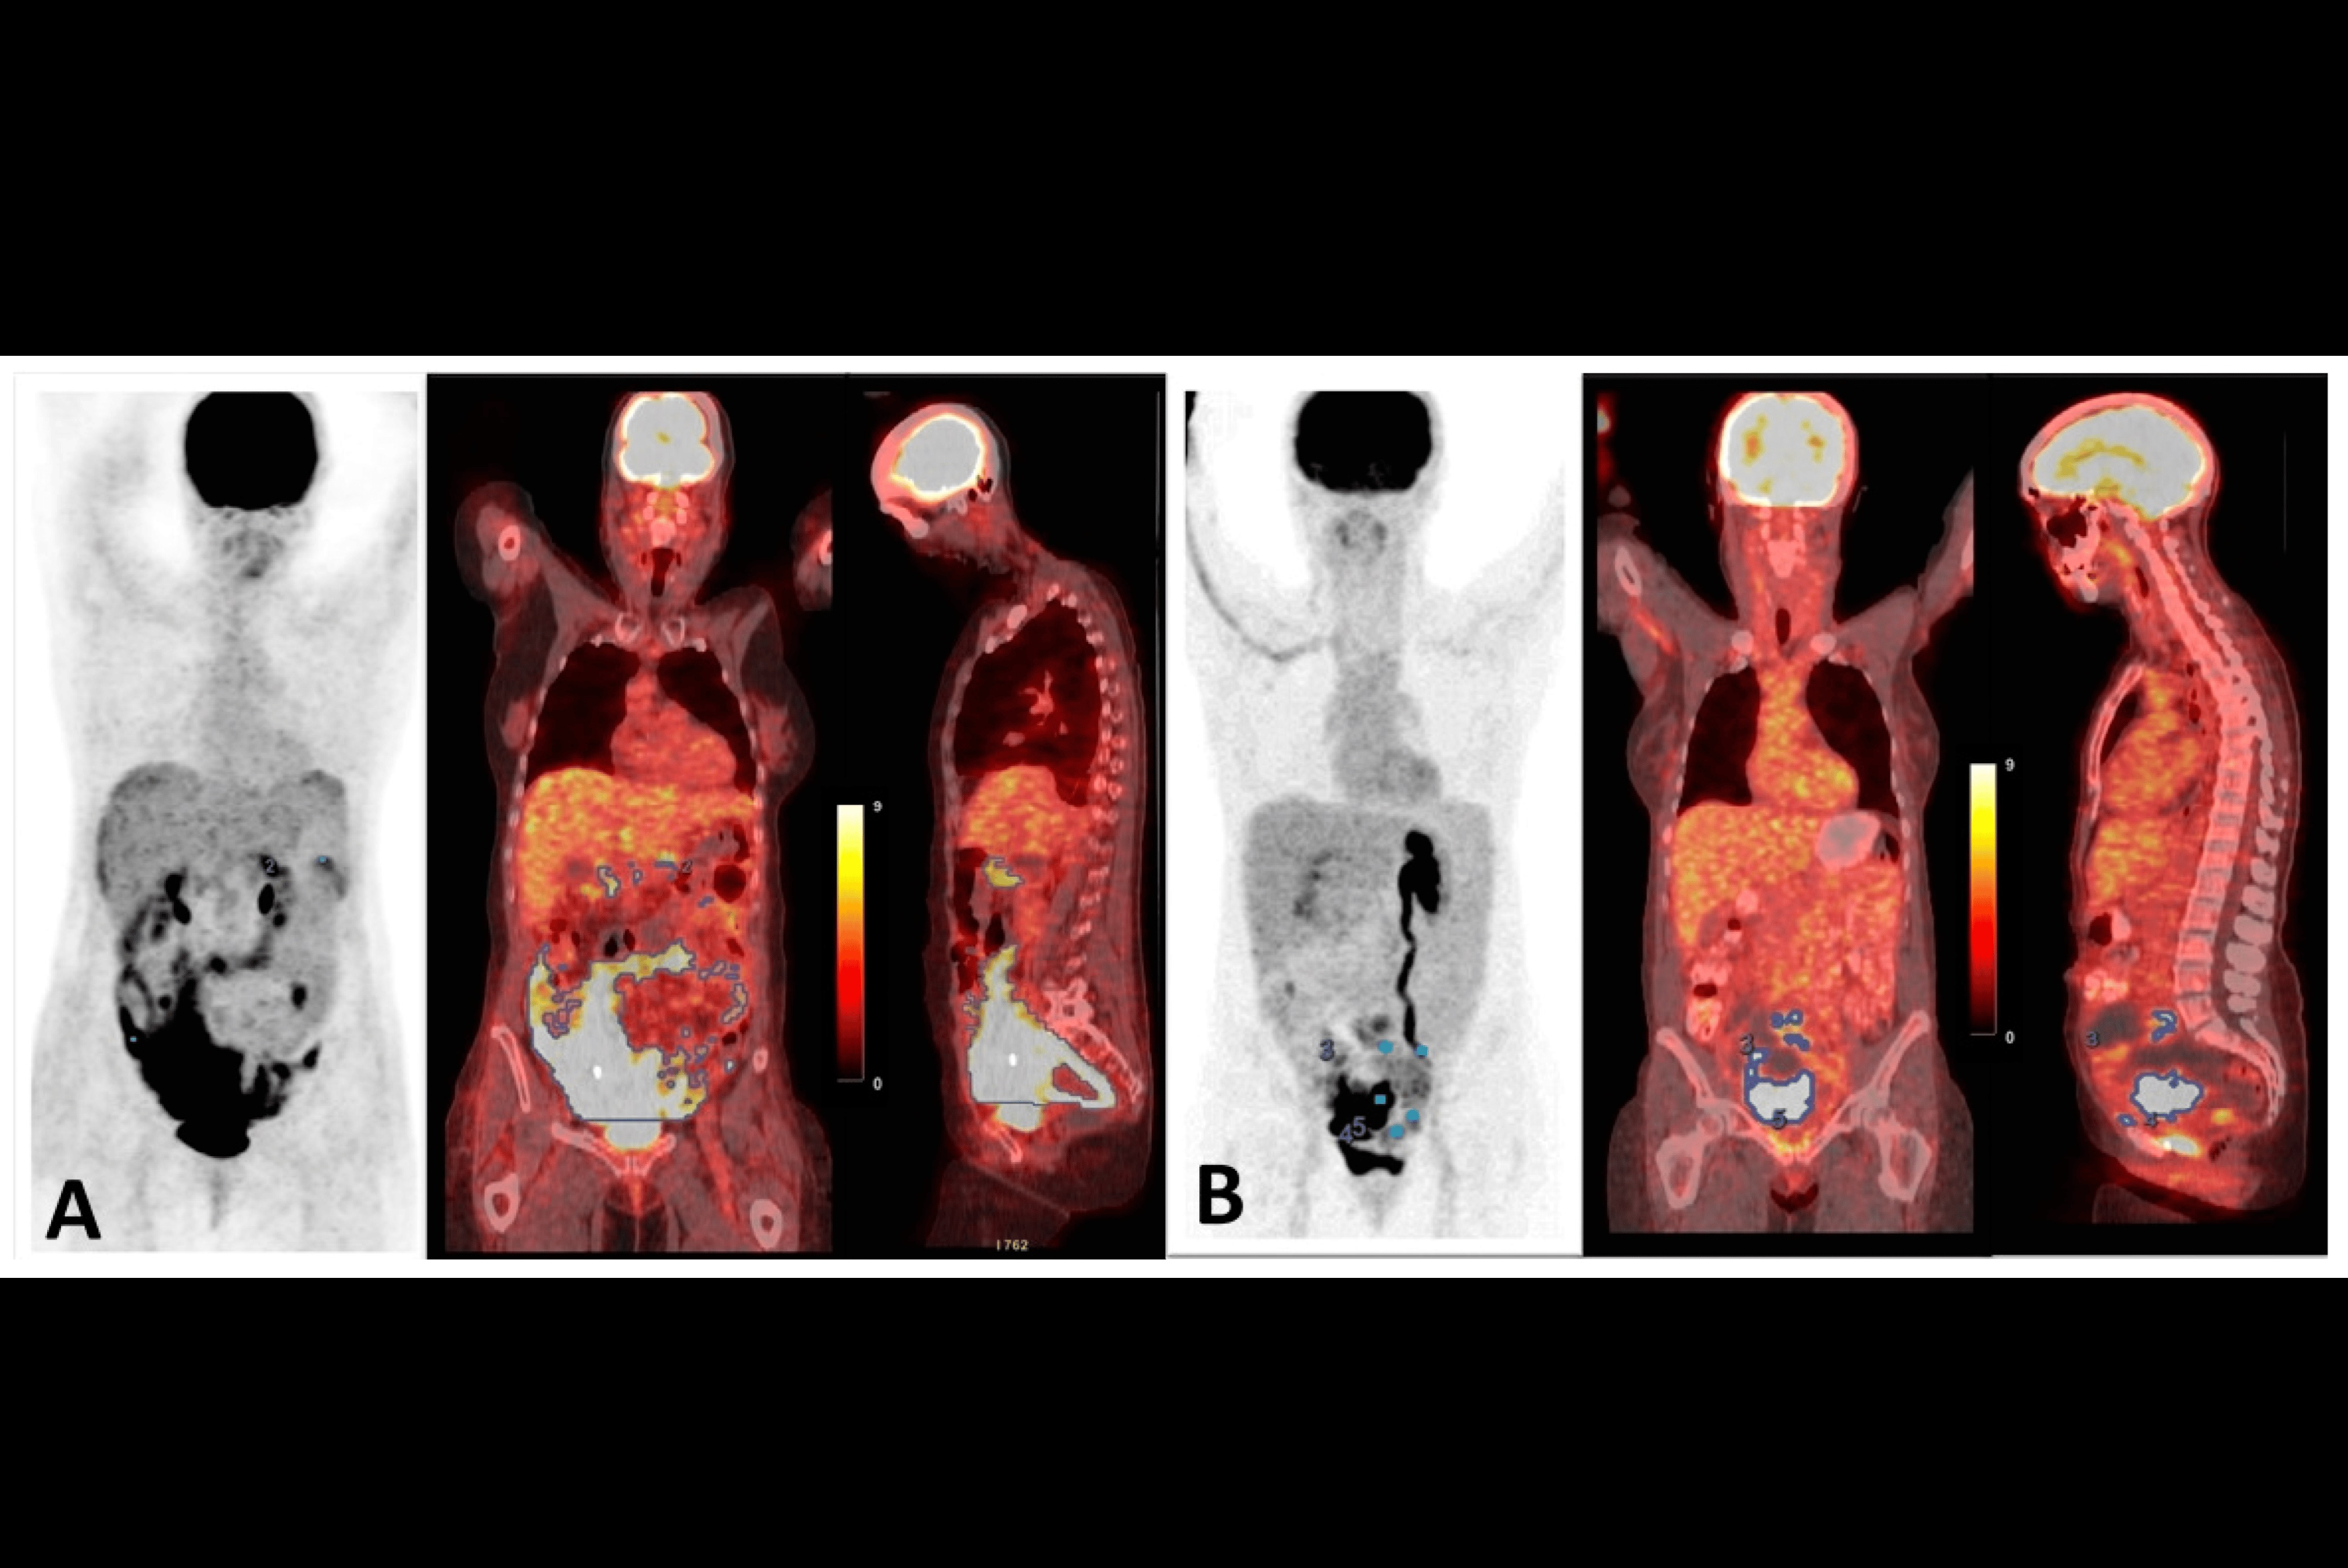

FAP is overexpressed by cancer cells, and research suggests it is an essential component driving the growth of tumors. When combined with medical isotopes such as gallium-68, radioligands that bind to FAP (radiotracers) have proven highly effective for visualizing cancer. FAP PET imaging has proven useful for initial staging, restaging, therapy response evaluation, and whole-body target expression assessment for therapy selection, the authors explained.

The guidelines outline several oncologic indications for FAP PET imaging, including gastrointestinal adenocarcinoma, pancreatic ductal adenocarcinoma, esophageal, head and neck cancer, thyroid, lung, and ovarian and breast cancers. In addition, it reviews the qualifications and responsibilities of imaging personnel and presents standardized quality control/quality assurance procedures and imaging procedures for FAP PET.